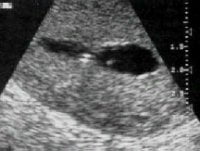

Asherman sendromunun rahim filmindeki ve sulu

ultrasonografideki görünümü